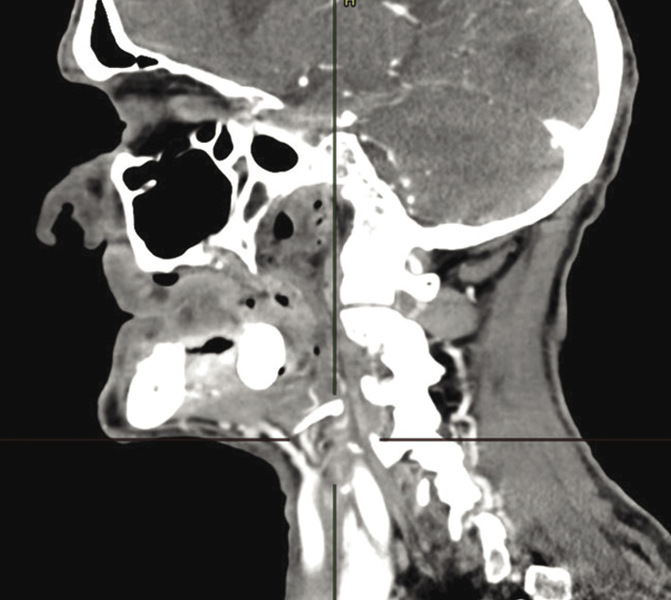

Pacjent został przyjęty 2 miesiące wcześniej na Oddział Otolaryngologii Szpitala w Lubinie, gdzie wykonano biopsję wycinkową zmiany nowotworowej dna jamy ustnej oraz badania obrazowe: tomografię komputerową (TK) twarzoczaszki i szyi z kontrastem, ultrasonografię (USG) jamy brzusznej oraz radiografię klatki piersiowej.

Ryciny 1-3 przedstawiają skany tomografii komputerowej twarzoczaszki i szyi z kontrastem, które szczegółowo dokumentują lokalizację oraz zaawansowanie zmiany nowotworowej. Ponadto materiał uzupełniają fotografie wykonane podczas zabiegu chirurgicznego, obrazujące zakres przeprowadzonej resekcji (ryc. 4 A-D).